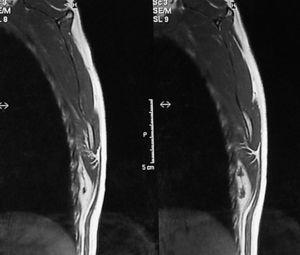

De las cuatro restantes tumoraciones infraescapulares estudiadas, reflejadas en la tabla 1, dos fueron liposarcomas, una fue un lipoma intramuscular y, la última, un hematoma asociado a rotura muscular. En todas ellas se planteó el ED como diagnóstico diferencial. En el caso 6 se halló una tumoración subescapular de unos 10 cm de diámetro en el contexto del estudio de una masa en el muslo derecho, cuya PAAF previa fue indeterminada, y que finalmente correspondió a un liposarcoma multicéntrico metastásico (fig. 7). El caso 7 correspondió a una masa escapular como diseminación de un liposarcoma mixoide en muslo (fig. 8). En el caso 8 se planteó el diagnóstico de elastofibroma por sus características clínicas, descartándolo tras una RMN y llegando al diagnóstico definitivo de lipoma intramuscular tras la resección (fig. 9). El caso 9 corresponde a un varón joven que presentaba una tumoración blanda y elástica en región subescapular de unos 5 cm de diámetro, de tres semanas de evolución y que molestaba con la tos. El estudio por ecografía fue suficiente para llegar al diagnóstico de ruptura muscular y hematoma secundario.

Figura 8. Diseminación escapular de un liposarcoma mixoide en muslo.